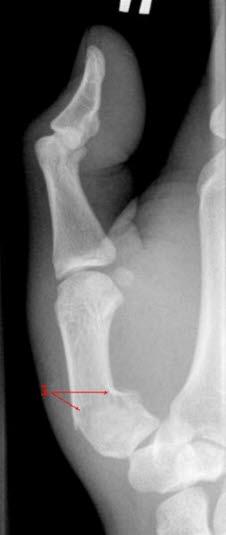

Brudd gjennom leddflaten i basis av 1. metakarp der skaftdelen av det brukne beinet dras ut av stilling fordi en kraftig muskel er festet til dette beinet, betegnes Bennet-bruddBrudd oppstår enten i metakarp-skaftet og/eller i leddhodet. To brudd har fått spesiell oppmerksomhet:

Etter forutgående skade blir hånden eller fingeren opphovnet og smertefull. Beinet kan ha blitt slått skjeivt, og diagnosen er da åpenbar. Et Bennet-brudd skyldes ofte et slag der tommelen tvinges bakover langs sin lengdeakse eller at den bøyes sterkt bakover (abduksjon). På samme måte oppstår et omvendt Bennet-brudd gjerne etter et slag der lillefingeren tvinges bakover langs sin lengdeakse eller at den bøyres sterkt bakover.

Ved Bennet-brudd er det hevelse og ømhet over 1. metakarp nær håndroten. Av og til er det tydelig feilstilling. Ved omvendt Bennet-brudd er det hevelse og ømhet over 5. metakarp på håndrotssiden.

Bennet-brudd må opereres fordi de er ustabile på grunn av sener som drar i bruddendene. Oftest festes de med pinnefiksasjon (Kirschner-pinner) og deretter gips i 6 uker. Etter at gipsen er fjernet, startes opptrening av håndfunksjonen.